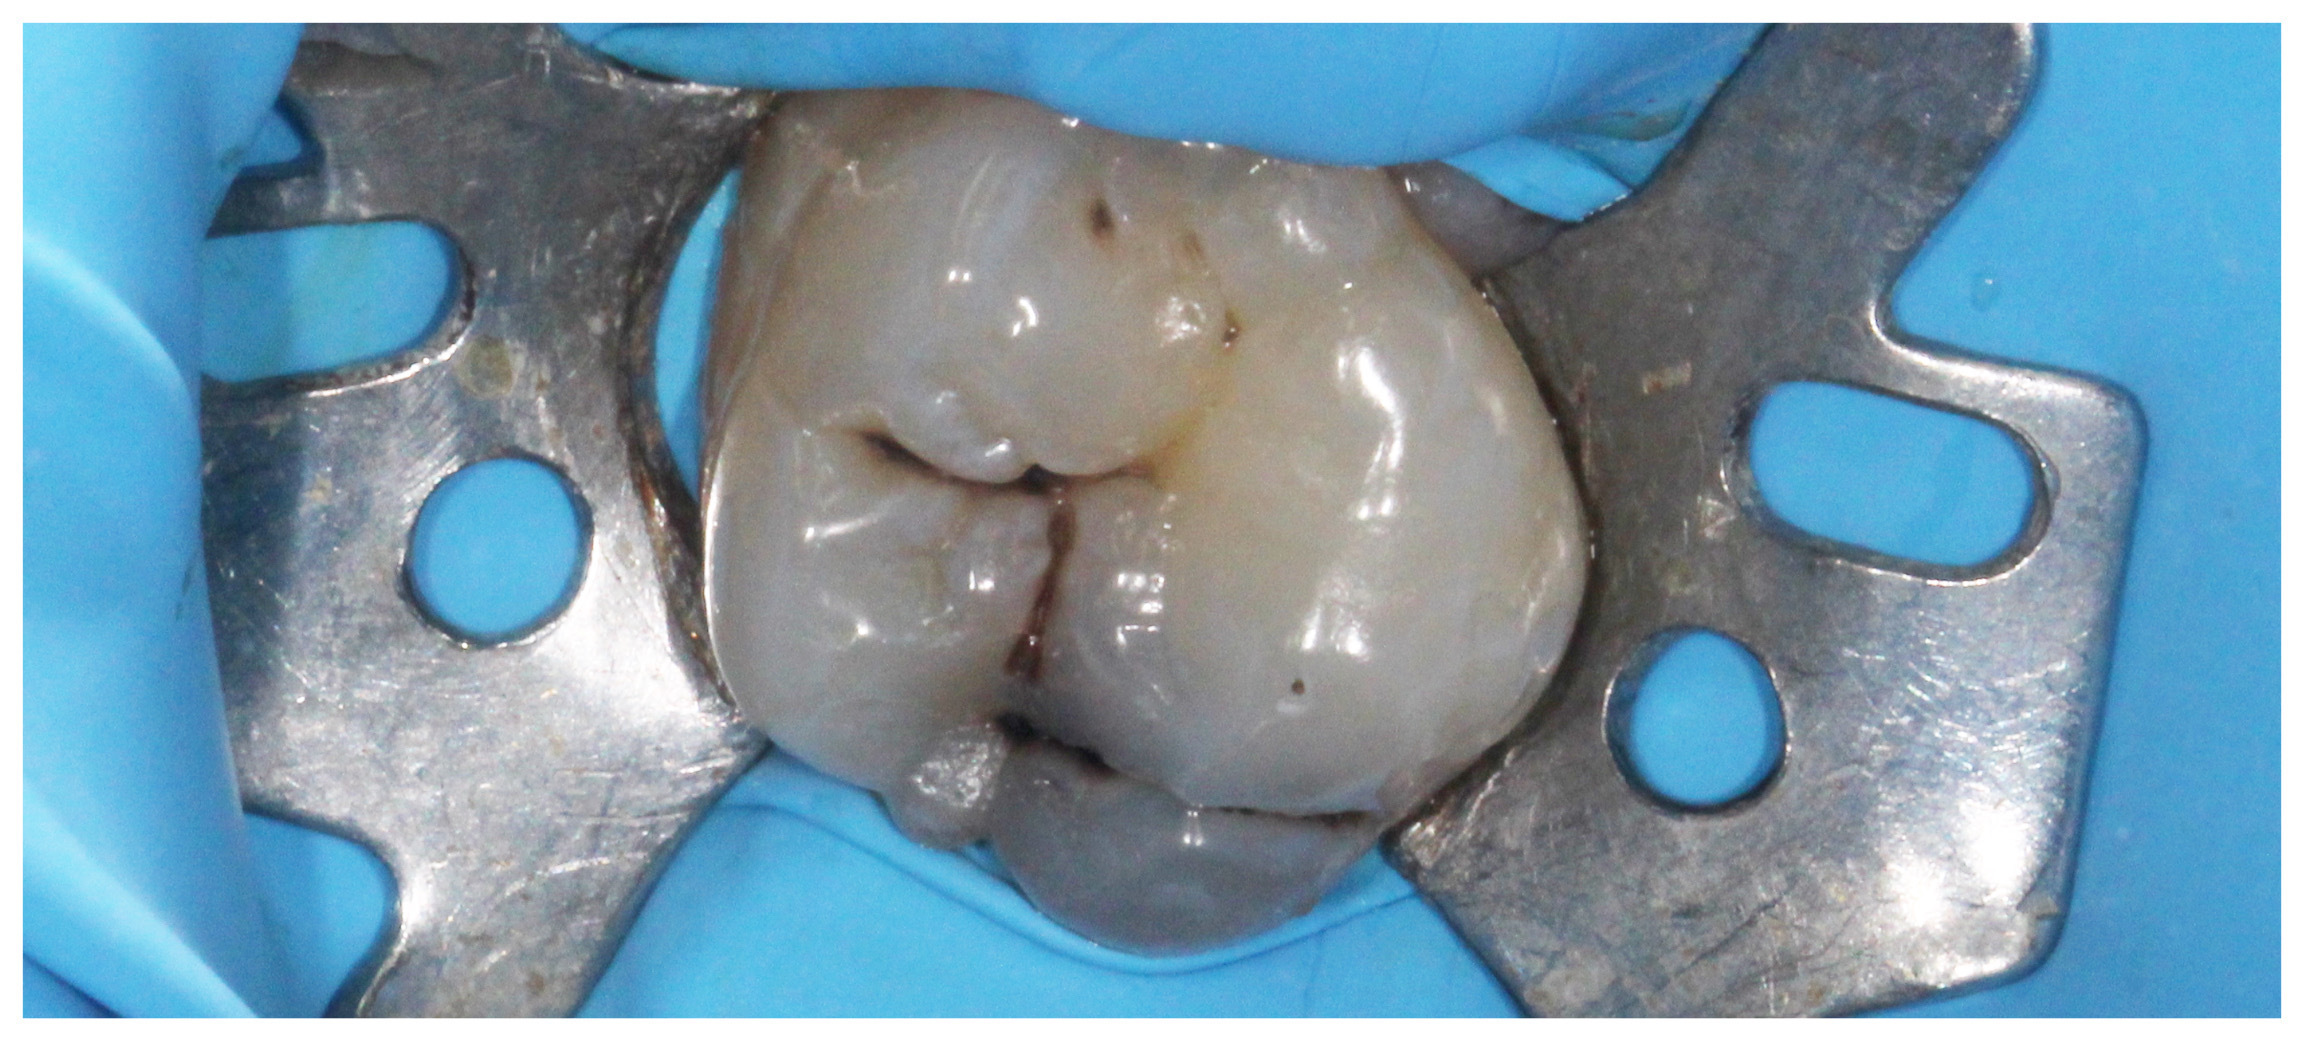

Primary caries on the upper first molar

Acces to the caries

Removed caries

Photocomposite filling